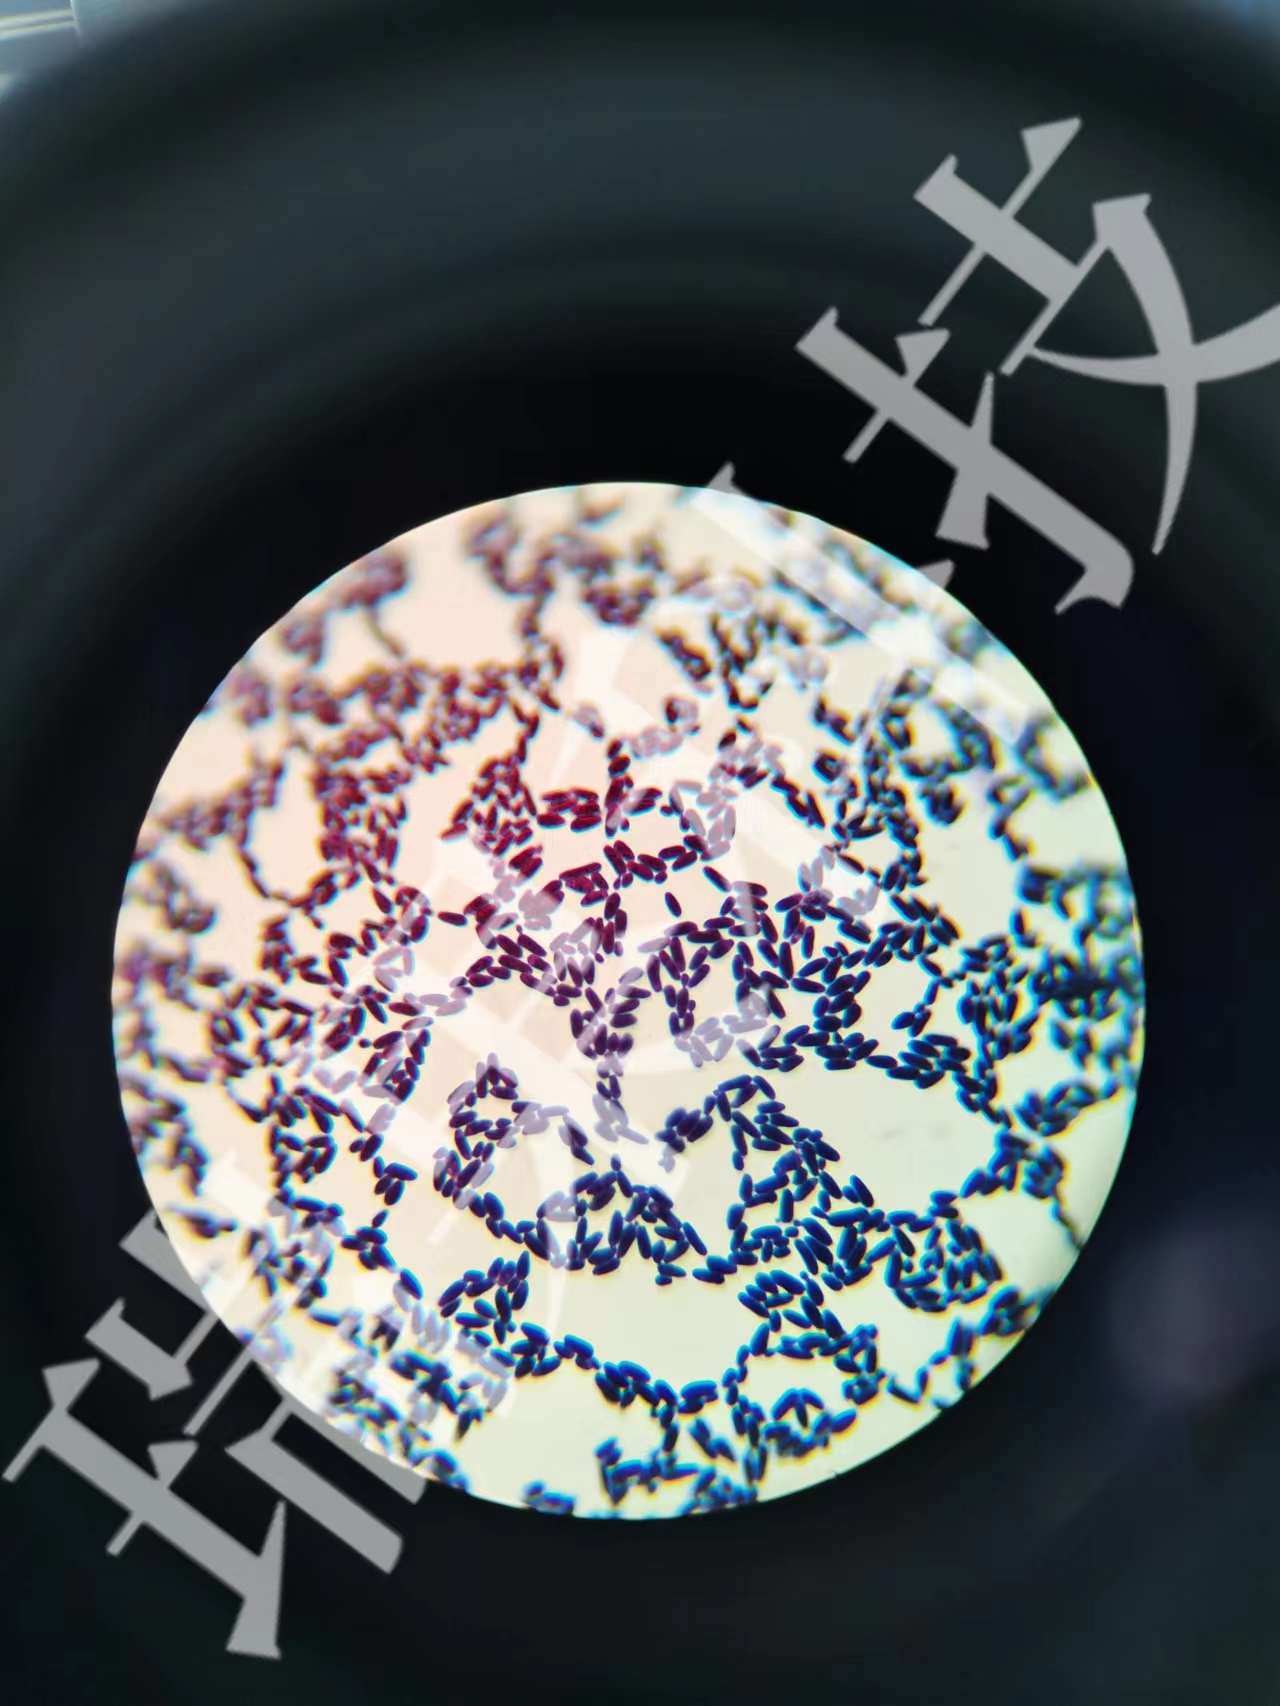

德氏乳杆菌革兰氏染色

德氏乳杆菌革兰氏染色 当前位置:首页 > 公司产品 > 产品服务 > 瑞果产品展示 > 细菌